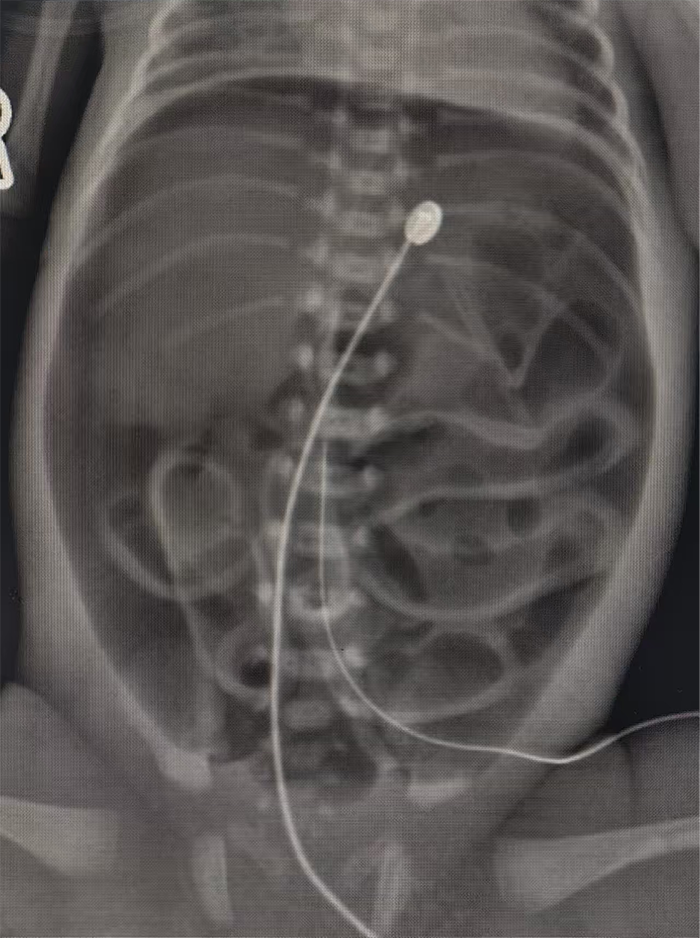

时间就是生命!医护人员立即启动紧急处置流程,床旁X光检查结果显示腹腔内存在大量游离气体,提示消化道穿孔可能。新生儿科第一时间联系小儿外科紧急会诊,小儿外科执行主任聂梅兰带领团队火速赶赴NICU,结合患儿临床表现、影像学检查结果,精准研判为胃破裂。